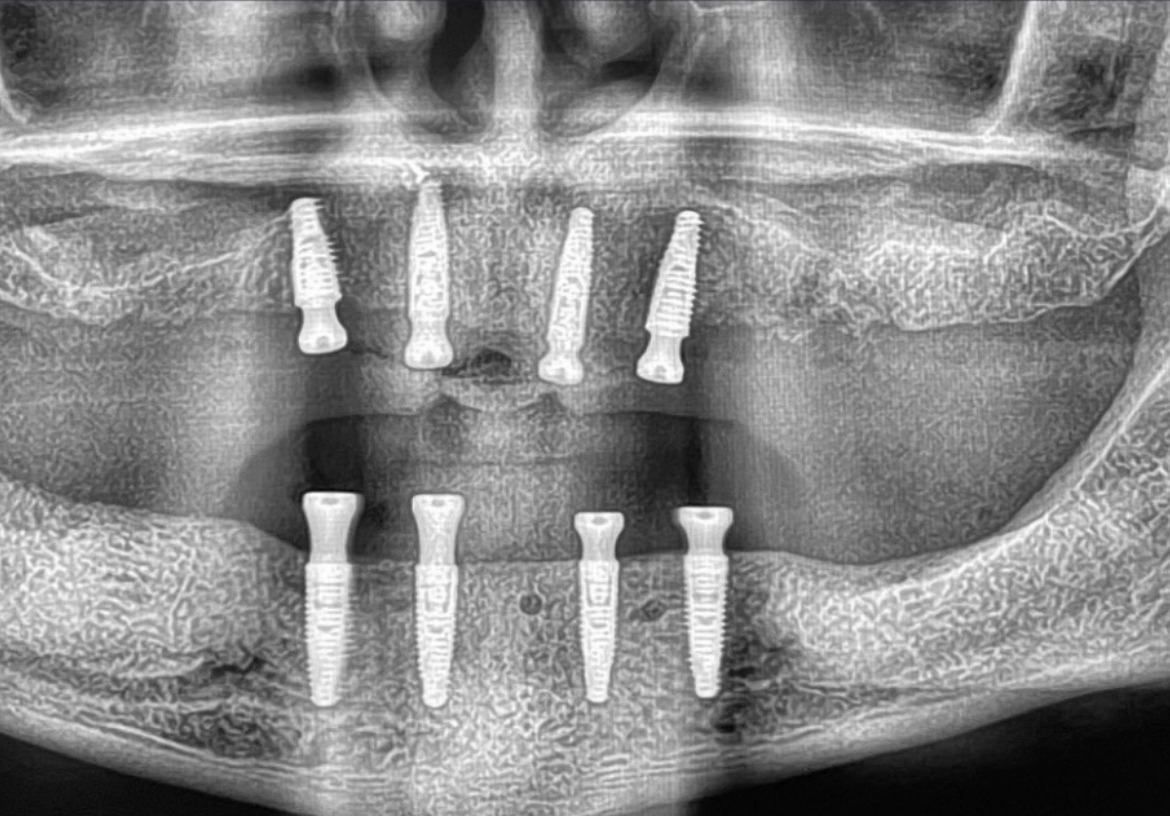

この患者様は上顎、下顎ともAll-on-4を同時に一日で行いました。

手術の前に残っていた歯はグラグラしていた為、手術当日に抜歯。すぐにインプラントを埋入しました。骨が安定するまで3ヶ月ほど仮歯で過ごしていただき、その後セラミックスのきれいな歯を装着します。